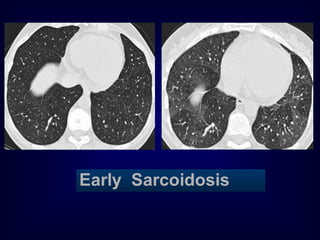

Early Sarcoidosis

Pathology in blackareas Airtrapping: Airway Disease Bronchiolitis obliterans (constrictive bronchiolitis) idiopathic, connective tissue diseases, drug reaction, after transplantation, after infection Hypersensitivity pneumonitis granulomatous inflammation of bronchiolar wall Sarcoidosis granulomatous inflammation of bronchiolar wall Asthma / Bronchiectasis / Airway diseases

Airway Disease what yousee…… In inspiration sharply demarcated areas of seemingly increased density (normal) and decreased density demarcation by interlobular septa In expiration ‘black’ areas remain in volume and density ‘white’ areas decrease in volume and increase in density INCREASE IN CONTRAST DIFFERENCES AIRTRAPPING